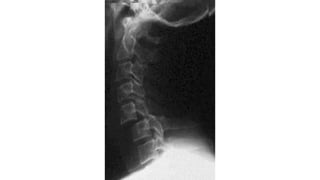

COLUMNA CERVICAL

• Una serie adecuada incluye:

• Proyección lateral de columnacervical con

rayo horizontal

• Deben visualizarse:

• Base de cráneo

• 7 vértebras cervicales.Valorar tracción de

hombros.

• 1ª vértebra torácica si es posible

• AP

• Proyección de odontoidescon boca abierta

• Sin movilizar al paciente

INTERPRETACIÓN DE LA RX.

ABCD

A: adecuada-alineada

B: hueso

C: cartílago

D: disco

S: tejidos blandos